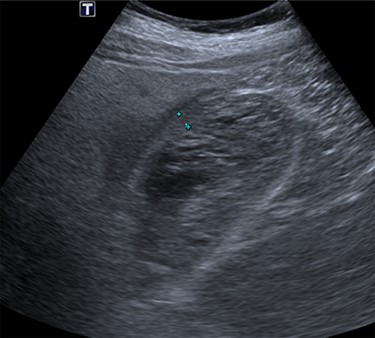

The patient was taken to theatre the second day of the admission. At laparoscopy, the gallbladder was visibly necrotic. The gallbladder was inadvertently perforated during retraction and a large volume haematoma was evacuated, as shown in Fig. 4. Dissection proceeded normally and the critical view was achieved. No intraoperative cholangiogram was performed due to the inflamed and friable nature of Calot’s triangle. The cystic duct and artery were clipped and cut, allowing the gallbladder to be dissected off the cystic plate. Surgicell was placed in the gallbladder fossa and a 15fr drain was secured. The drain was subsequently removed the day following operation, and on Day 2, the patient was discharged on a normal diet, having restarted apixaban.

Photo taken intraoperatively, demonstrating haematoma leaking from a necrotic gallbladder.